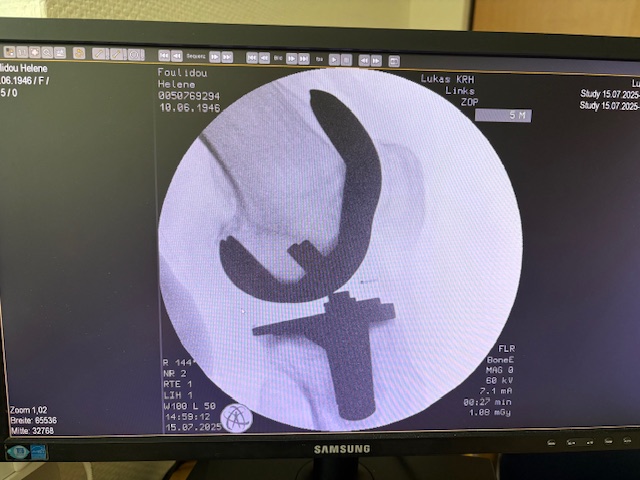

Η επέμβαση πραγματοποιήθηκε με ρομποτικά υποβοηθούμενη τεχνική, κατά την οποία το ρομποτικό σύστημα με καθοδήγησε με ακρίβεια χιλιοστού σε κάθε στάδιο.

Έτσι εξασφαλίστηκε η ιδανική τοποθέτηση των εμφυτευμάτων, η αποκατάσταση του μηχανικού άξονα και η διατήρηση των μαλακών ιστών.

Τα εμφυτεύματα που χρησιμοποιήθηκαν στο γόνατο της ασθενούς είναι της Aesculap: E-Motion Pro, μηριαίο μέγεθος 4, κνημιαίο μέγεθος 4, με ενθέμα (inlay) 10mm.

Η επέμβαση ολοκληρώθηκε χωρίς επιπλοκές, με ελάχιστη απώλεια αίματος και ταχεία κινητοποίηση της ασθενούς.